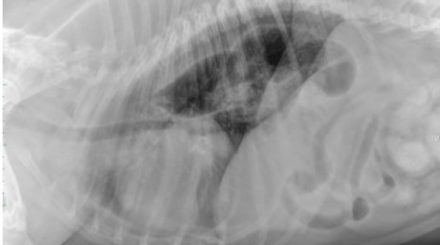

Radiography Reading ‘Abdominal Imaging’ (22/07/2025)

Our radiography reading sessions are a great way for our Specialists to bring new and interesting diagnostic imaging conundrums for discussion with our vtx community. In this session, the theme…